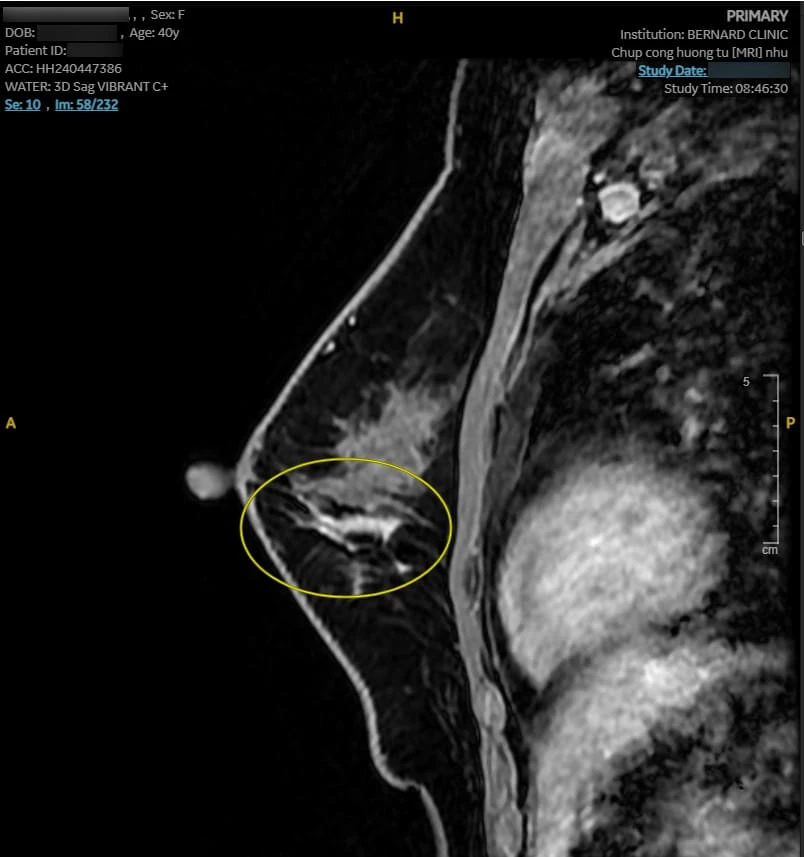

Hình ảnh MRI cho thấy nhiều bất thường. Vú phải có nang vú vị trí 6 giờ, cách núm vú 3cm, d-7mm, phân loại BI-RADS 2. Vú trái có bất thường tín hiệu diện rộng 1/2 dưới (6 - 8 giờ), giới hạn bờ kém rõ, tổn thương dạng đám/nốt/đường, BI-RADS 4.

| Hình ảnh tổn thương qua MRI với Coil Nhũ chuyên biệt, chụp tại Bernard Healthcare |